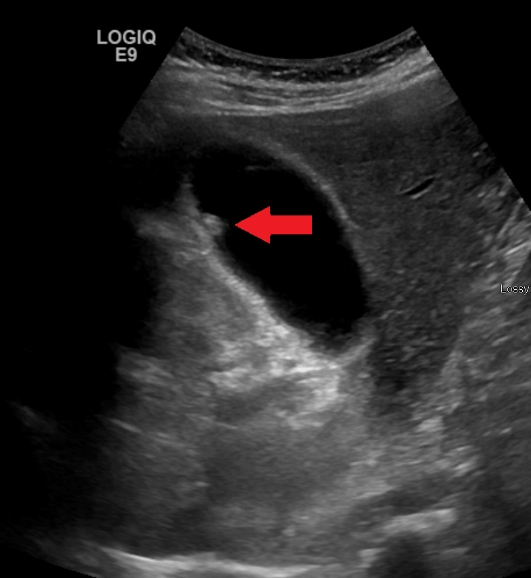

담낭 용종 진단하기

탐정이 수수께끼를 푸는 것처럼 의사도 담낭 용종이 있는지 알아낼 수 있는 방법이 있습니다.

의사는 초음파 기계와 같은 도구를 사용할 수 있는데, 이는 신체 내부를 사진으로 찍는 것과 같습니다. 이를 통해 담낭에 용종이 있는지 확인할 수 있습니다.